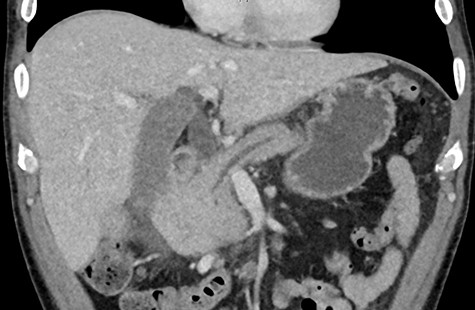

A retroperitoneal percutaneous biopsy of the retrocaval lymph node mass was performed without any complications. Awaiting histological diagnosis, his gastric outlet obstruction worsened, and hyperbilirubinemia increased to 317 umol/L, developed acute renal failure with creatinine rising to 484 umol/L and progressive anuria. The renal failure was believed to be multifactorial from malignancy and cholemic nephropathy that can be seen in patients with obstructive jaundice [2]. The patient was transferred to HDU (High Dependency Unit) for haemodialysis. Histopathology results confirmed a poorly differentiated high-grade RCC of clear cell subtype. Endoscopic examination performed confirmed an infiltrating obstructive duodenal mass and a self-expanding ‘Wallflex’ duodenal stent was inserted. As retrograde access for biliary stenting was near impossible, a percutaneous transhepatic cholangiography (PTC) was performed with anterograde stenting of the bile duct resolving the hyperbilirubinemia (Fig. 3). Over the following days the patient’s hyperbilirubinemia and renal failure normalized. He recovered uneventfully and was subsequently commenced on immunotherapy prior to discharge.

(PTC) Anterograde biliary stent through duodenal wall flex stent.